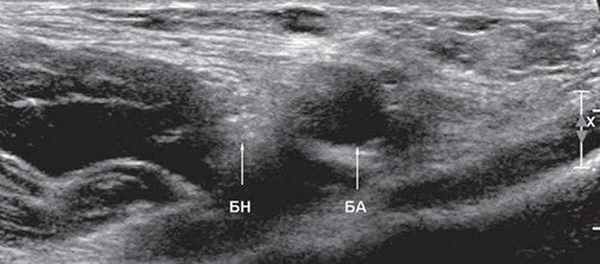

УЗИ бедренного нерва проводили в положении пациента лежа на спине. Бедренный нерв визуализировали в паховой области латеральнее сосудистого пучка от уровня паховой связки до верхней трети бедра (рис. 2, 3). Исследование проводили в поперечной и продольной плоскостях сканирования (рис. 2, 4).

Рис. 2. В-режим. Исследование правого бедренного нерва в поперечной плоскости сканирования на уровне паховой области: БН - бедренный нерв, БА - бедренная артерия.